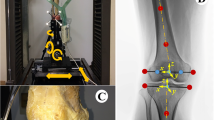

The main finding of this study was that the knee laxity increased substantially, both in flexion and, unexpectedly, also in extension with more posterior tibial slope in case the ACR technique was simulated. In contrast, varying the tibial slope with the CPR technique had little effects on knee laxity. The tension of the TFJ ligaments during simulated squat decreased with more posterior tibial slope for both referencing techniques, indicating a progressive loosening of the TFJ gap with more posterior slope, although the changes were more distinct with the ACR technique. Also a previous study found decreased PCL strain with more posterior tibial slope [22]. No aberrant TFJ contact point movements were observed during simulated squat, even with large degrees of posterior tibial slope, when the CPR technique was simulated. This is in agreement with a previous fluoroscopic study on knee kinematics during stair ascent, getting up from and sitting down on a chair and single-leg climbing up a step [6], in which the original slope was restored and the post-operative slope ranged from −2° to 10°. Therefore, the concern for increased risk of wear, due to extreme roll-back with more posterior tibial slope [24], does not appear much justified, based on results of this study, as long as the TFJ gap is successfully balanced in both flexion and extension. In contrast, more slope with the ACR technique resulted in larger excursions of the TFJ contact point in extension on both medial and lateral side, owing to a loosened TFJ gap, which in turn may lead to increased wear of the polyethylene insert. A more posterior location of the TFJ contact point can, in principle, increase the quadriceps moment arm and reduce the quadriceps force [7, 10]. Previous studies found more posterior TFJ contact point (in vivo) [12] and reduced quadriceps forces (ex vivo) [21] with more posterior tibial slope. In the present study, the peak quadriceps forces were reduced during squatting with more posterior tibial slope with both referencing techniques. The patella shifted superiorly relative to the femur condyles with more posterior tibial slope with the ACR technique, due to lowering of the TFJ line. This reduced the force exchanged between quadriceps tendon and femoral condyles by wrapping (Fig. 7, centre). With the CPR technique, the patellar height remained unchanged, and the quadriceps–femur load sharing was preserved. Also the PFJ contact force was more effectively reduced with more posterior tibial slope with the CPR technique (−12% BW every 3°) relative to the ACR technique (−5% BW every 3°). Although the difference was relatively small, decreased PFJ contact forces may contribute to reduce anterior knee pain and implant wear [3] after following CR-TKA.

Conceptual representation of the quadriceps–femur (QF) and patella–femur (PFJ) load sharing with +9° of tibial slope with a anterior tibial cortex referencing (ACR) and b centre of tibial plateau referencing (CPR) techniques. The quadriceps muscle force decreases with more posterior slope both with ACR and CPR techniques. However, with ACR the position of the patella relative to the femur condyles is higher than with CPR, and a much lower quadriceps force can be transmitted via the quadriceps tendon directly through the femur, thus the patella–femur force is reduced only by a little amount; with CPR technique the amount of quadriceps force transmitted through the femur is higher, thus the patella–femur force is reduced more importantly